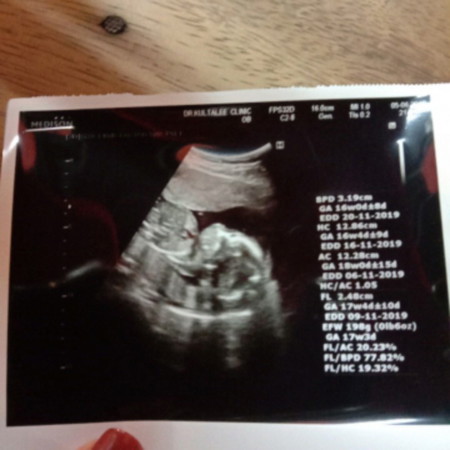

สอบถามแม่ๆที่เคยไปซาวด์ช่วง 17-18 วีคหน่อยค่ะ ลูกมีสรีนะพุงป่องๆโตๆไหมคะ ของเราเป็นแบบในภาพพอไปเทียบกับเพื่อนๆลูกเพื่อนๆเขาพุงไม่ป่องขนาดนี้อะคะ

ถ้ามีไรผิด ปกติ หมอ จะ อธิบายหลังที่อันตราซาว์ เสร้จ เลยค่ะ แต่ถ้าไม่ ก้แสดงว่า ปกติ ดีค่ะ

เด็กแต่ละคนไม่เหมือนกันค่ะ. ถ้าซาวแล้วมีสิ่งผิดปกติหมอจะบอกอยู่แล้วค่ะ.

ตอนซาวน์หมอไม่อธิบายหรอค่ะแม่ ถ้าหมอบอกปกติก็ปกตินะคะอย่ากังวลไปเลยนะคะ